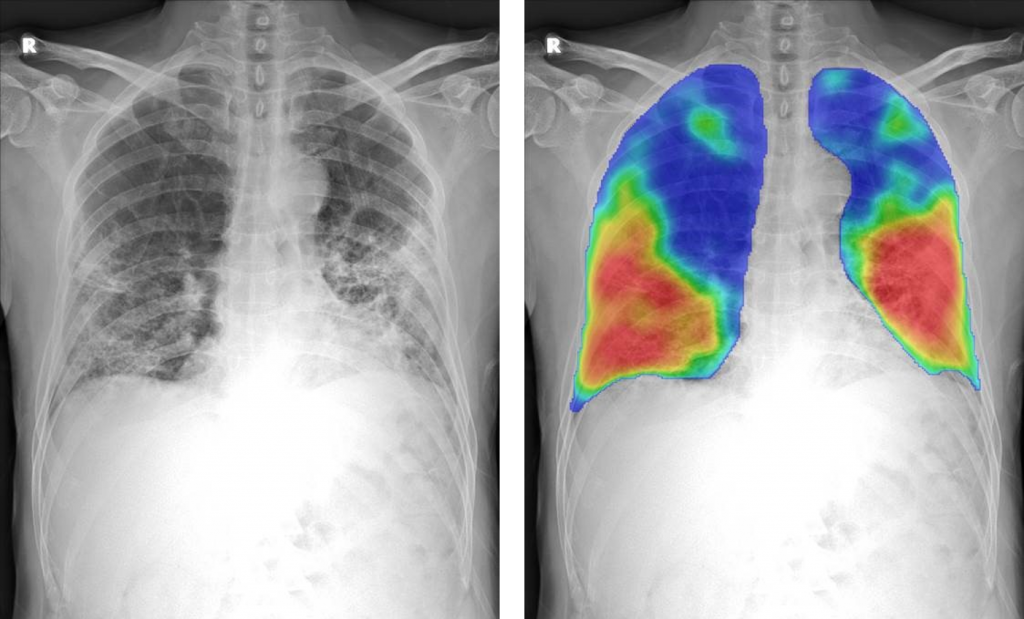

CAD4COVID will generate a score between 0 and 100 indicating the extent of COVID-19 related abnormalities, display such lung abnormalities through a heatmap and quantify the percentage of the lung that is affected.